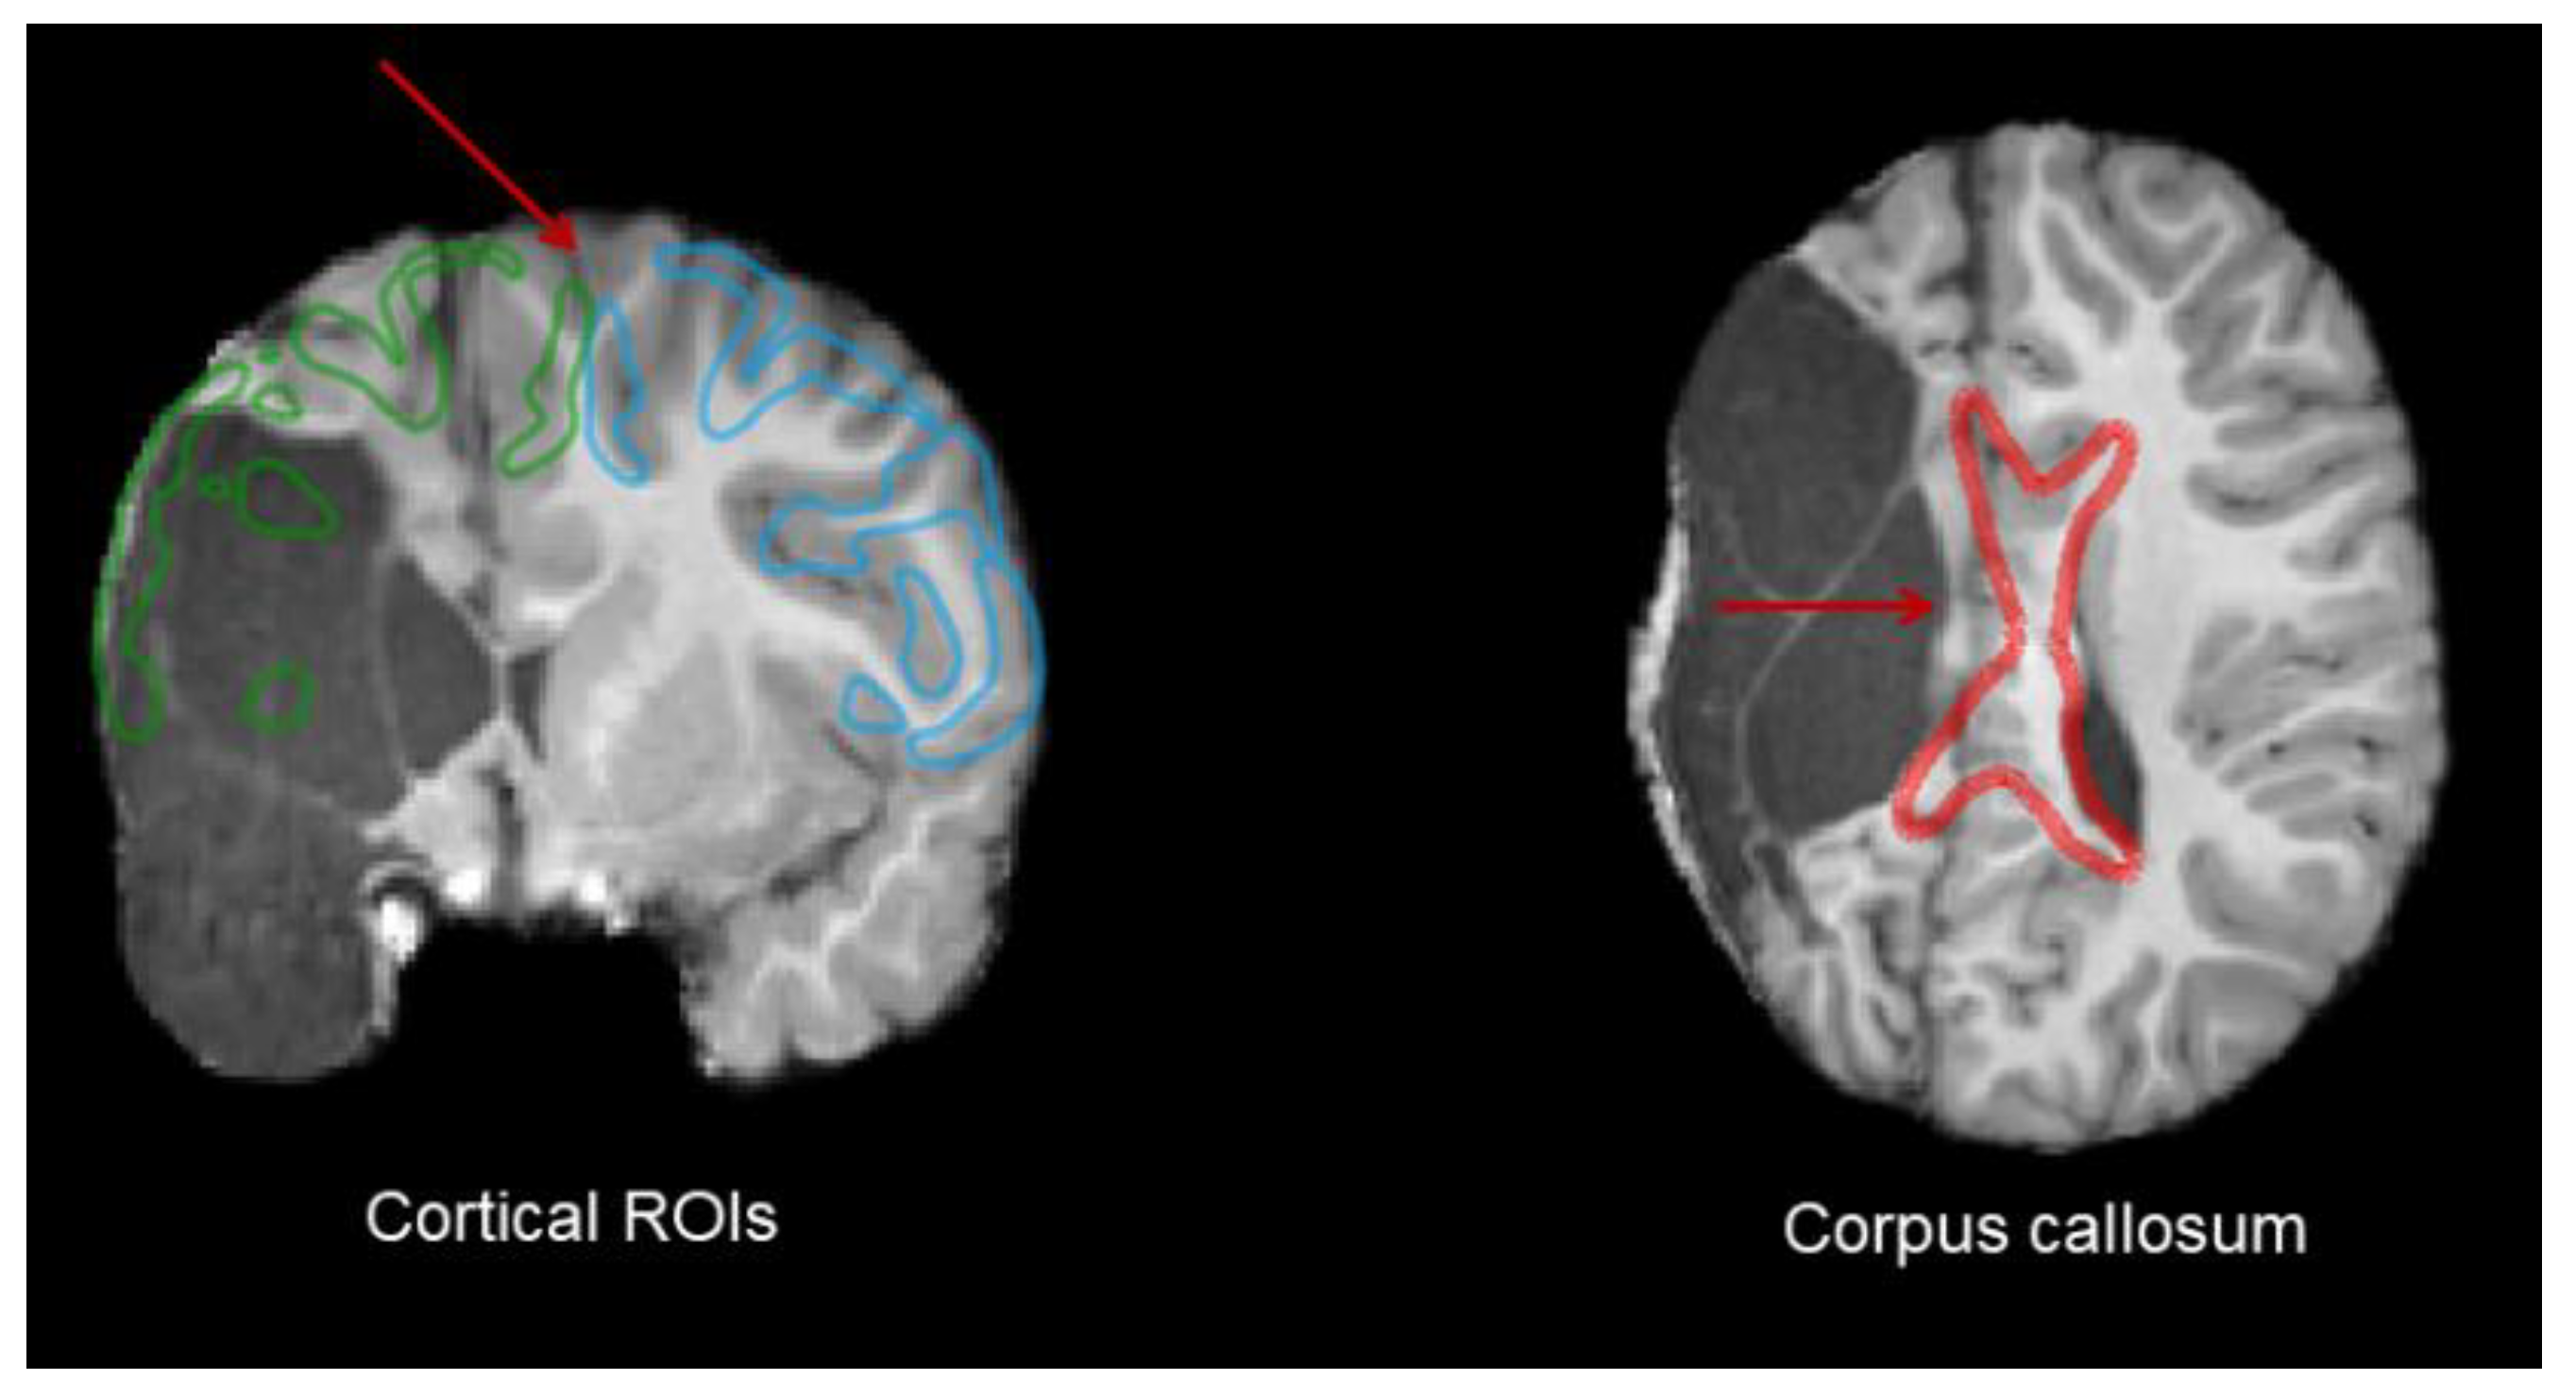

Automatic Extraction

Atlas-Based Customized Extraction

- ROI and Bundle Extraction

2.4. Lesion Characterization